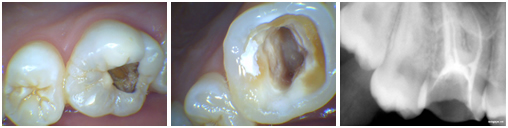

• If your “decay” is in the enamel and dentin layer of the tooth we can save your tooth by filling your tooth.

• But if the tooth decay is deep and it reach up to pulp then your whole tooth become infected up to the end of the root then we remove that pulp of tooth, clean the all canals in tooth and fill it by artificial nerves – “Gutta Purcha” like material and put a capping (Crown) over that. This procedure is called ROOT CANAL TREATMENT (R.C.T.)